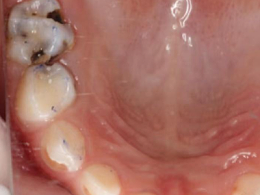

很多家长存在一个误区:乳牙迟早要换,不用涂氟,浪费时间和精力 。其实,这种想法大错特错,乳牙的健康直接影响孩子的口腔发育和恒牙的健康,一旦乳牙出现蛀牙,不仅会让孩子承受疼痛,还可能影响恒牙萌出,导致恒牙排列不齐、牙釉质发育不全等问题。河北惟德口腔专注儿童口腔健康,用专业的涂氟服务,守护孩子乳牙健康,为恒牙发育打下坚实基础。

首先科普口腔知识:儿童乳牙的牙釉质比成人恒牙更薄、矿化程度更低,就像一层薄脆的蛋壳 ,抵抗酸腐蚀的能力特别弱,再加上孩子普遍爱吃甜食、喝奶后清洁不及时、刷牙配合度低,口腔里的细菌会分解食物残渣产生酸性物质,慢慢侵蚀牙釉质,最终形成蛀牙。而定期涂氟,能给乳牙穿上一层 防护铠甲 ,不仅能增强乳牙牙釉质硬度,还能抑制细菌产酸,修复牙齿早期的微小损伤,有效预防乳牙蛀牙。